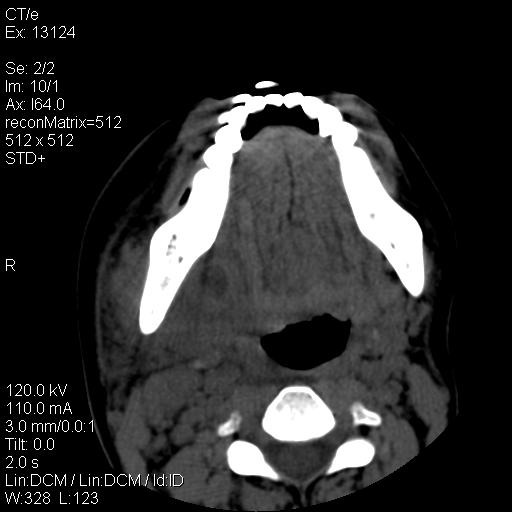

标题: CT18257:女,29岁,右下磨牙痛 [打印本页]

标题: CT18257:女,29岁,右下磨牙痛

女,29岁,右下磨牙痛,因产后2月,故未治疗。现右颌肿痛伴张口困难。请大家看看右侧鼻咽部、口咽部是否

1.考虑右侧下颌区脓肿(牙源性)

考虑右下智齿冠周炎伴周围软组织炎症,脓肿形成

1)考虑右侧下颌区软组织脓肿(牙源性)。2)鼻咽部炎性改变;建议追踪复查。3)右侧上颌窦炎。4)双侧下鼻甲黏膜肥厚。

1)考虑右侧下颌区牙源性软组织脓肿。2)右侧上颌窦炎。3)双侧下鼻甲黏膜肥厚。4)鼻咽部炎性改变;建议追踪复查。

考虑右下智齿冠周炎伴周围软组织脓肿形成。